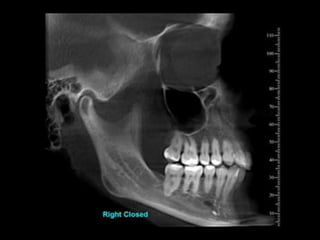

Ankylosis treated with total joint prosthesis

Panoramic view shows prosthesis (arrow), consisting of artificial fossa (fixed with six

titanium screws in temporal bone), and artificial condylar process (fixed with seven titanium

screws to mandibular ramus